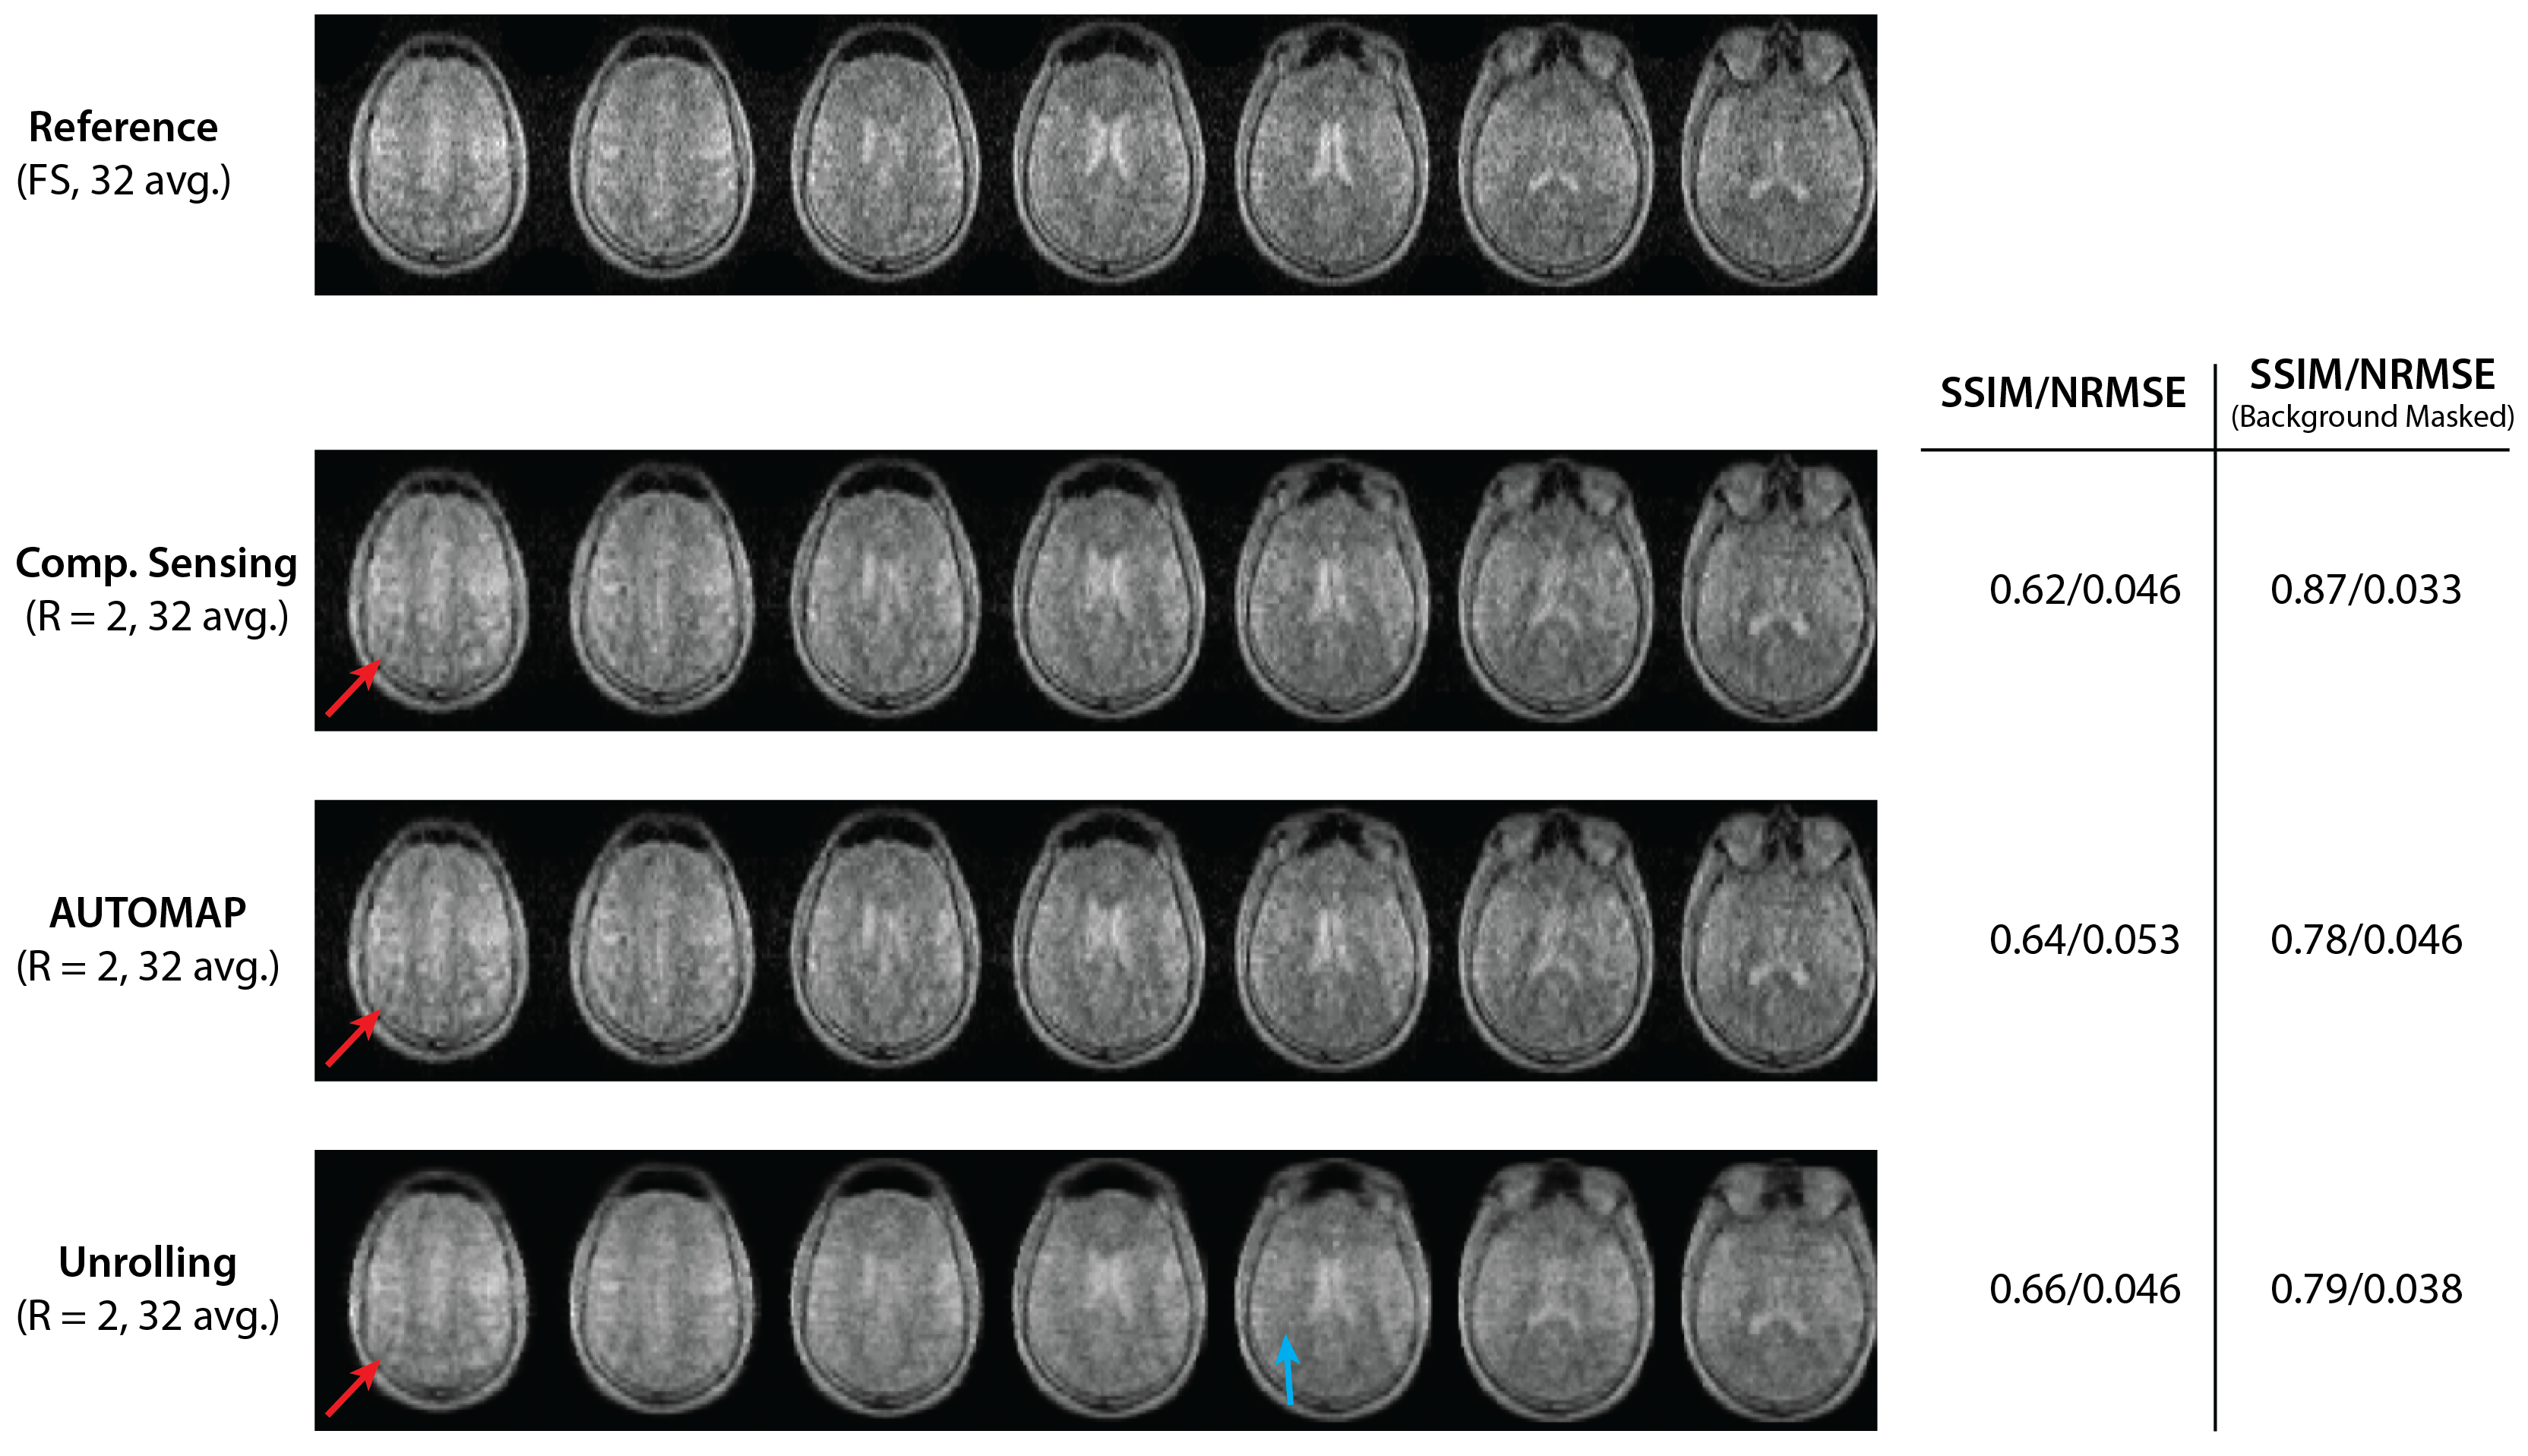

Undersampled fastMRI brain images were successfully reconstructed with the NRMSE of different reconstruction methods shown in Figure 1. At low SNR, Unrolling and AUTOMAP reconstruction methods outperform CS and IFFT techniques. CS gives the best NRMSE at high SNR. Comparing reconstructions for an input SNR of 60 dB in Figure 2, we find that background noise is strongly suppressed by neural-network reconstruction. After masking the background, we find CS and Unrolling metrics to be equivalent.

Figure 1: The normalized root mean square error (NRMSE) of images reconstructed from undersampled ($$$R~=~2$$$), low-resolution FastMRI k-space data at different input SNR values. The SNR of the input signal (k-space) was adjusted by adding synthetic Gaussian noise scaled to the ground truth k-space data. Zero-filled Inverse Fast Fourier Transform (IFFT) and Compressed Sensing (CS) approaches are compared to AUTOMAP and Unrolling network techniques.